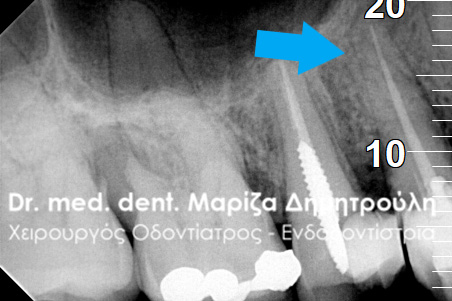

Ο ασθενής επιθυμούσε την προσθετική αποκατάσταση (με θήκη / στεφάνη δοντιού) του πρώτου γομφίου στην αριστερή πλευρά της κάτω γνάθου, καθώς το δόντι αυτό είχε ένα παλιό σφράγισμα το οποίο συνεχώς έσπαζε. Απαραίτητη προϋπόθεση για την έναρξη της διαδικασίας για τη στεφάνη δοντιού ήταν η κλινική και ακτινογραφική εξέταση του γομφίου. Μετά τη λήψη ακτινογραφίας αποκαλύφθηκε οτι το δόντι είχε μία παλιά απονεύρωση, η οποία ήταν ατελής εφόσον δεν εκτεινόταν σε όλο το μήκος των ριζικών σωλήνων του δοντιού ενώ φαινόταν ο τρίτος ριζικός σωλήνας στο δόντι να μην έχει εντοπιστεί. Μετά από συνεννόηση με τον ασθενή αποφασίστηκε η επανάληψη της απονεύρωσης του δοντιού, ώστε να εξασφαλιστεί ένα εγγυημένο προσθετικό αποτέλεσμα. Γενικότερα είναι επιθυμητό οι προσθετικές εργασίες να τοποθετούνται στα δόντια εφόσον έχουν γίνει όλες οι απαραίτητες εργασίες όπως απονεύρωση δοντιού, καθαρισμός των ούλων κ.α.

Μετά λοιπόν την αφαίρεση του παλιού σφραγίσματος εντοπίστηκε ο τρίτος ριζικός σωλήνας που δεν είχε βρεθεί στην παλιά πρώτη απονεύρωση, όπως δείχνει και η φωτογραφία της αρχικής κλινικής εικόνας. Στη συνέχεια καθαρίστηκαν και επεξεργάστηκαν όλοι οι ριζικοί σωλήνες (Για περισσότερες πληροφορίες Βλέπε Επανάληψη απονεύρωσης). Η διαδικασία ολοκληρώθηκε με την έμφραξη των ριζικών σωλήνων του δοντιού και την ανασύσταση της εκτεταμένης κοιλότητας με ειδικό άξονα υαλονημάτων και ρητίνη. Ακολούθως το δόντι τροχίστηκε, λήφθηκαν αποτυπώματα και όταν ο οδοντοτεχνίτης είχε έτοιμη τη θήκη του δοντιού αυτή κολλήθηκε στο δόντι.

ΠΡΙΝ